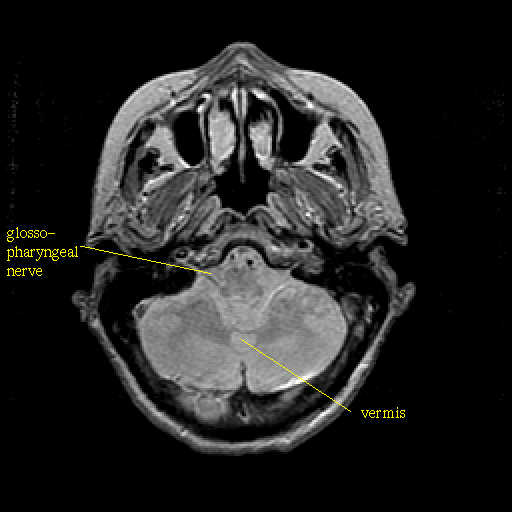

Proton density-weighted structural MR: Slice 11

Slice 11